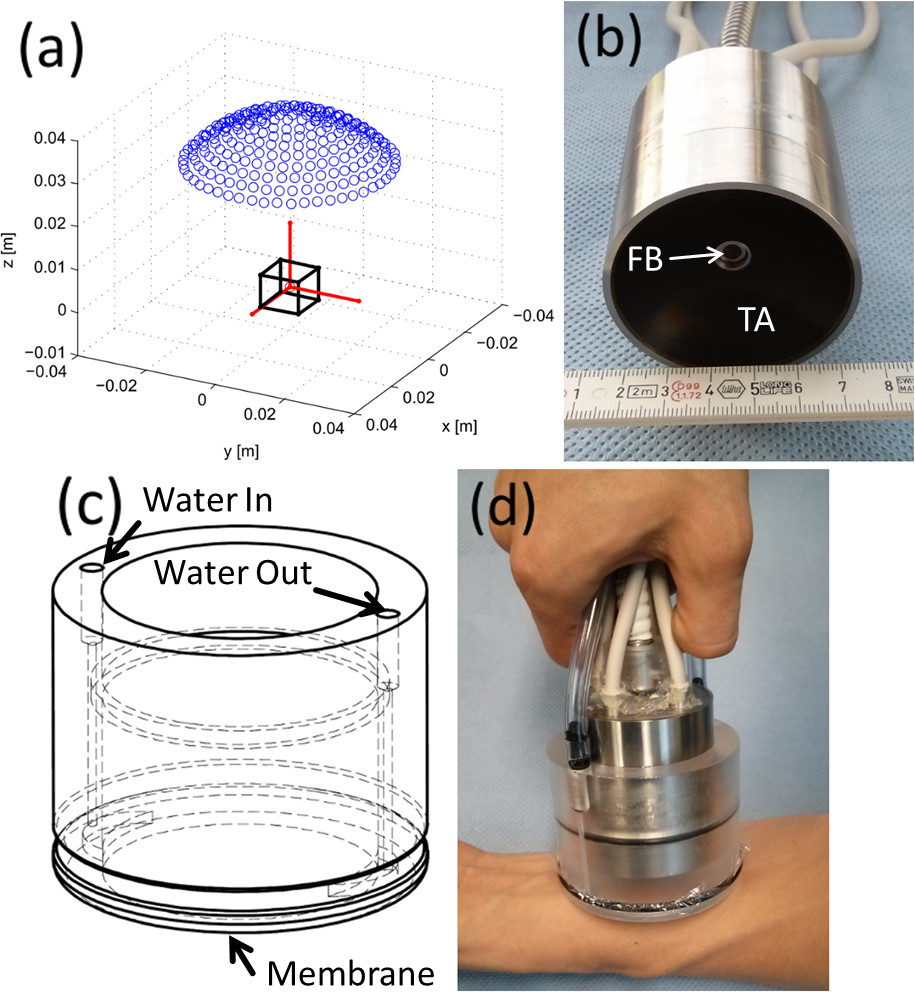

Recently, we introduced the first handheld optoacoustic probe for three-dimensional (volumetric) imaging in real time16. The system is based on a two-dimensional array of 256 piezoelectric elements arranged upon a spherical surface (blue dots in Figure 1A) covering an angle of 90°. The size of the individual elements of approximately 3 x 3 mm2, as well as their orientation and frequency bandwidth (approximately 2-6 MHz) guarantee effective signal collection from a centimeter-scale volume surrounding the center of the sphere (black cube in Figure 1A). Optical excitation of the imaging region is provided with a fiber bundle inserted through a central cylindrical cavity of the array, so that any wavelength susceptible of being transmitted through the fiber bundle can be used for imaging. An actual picture of the array of transducers along with the optical fiber bundle is shown in Figure 1B. The efficient excitation and simultaneous detection of signals allows deep-tissue imaging with single-shot excitation (one laser pulse), so that real-time imaging at a frame rate determined by the pulse repetition frequency of the laser is further enabled with a graphics-processing-unit (GPU) implementation of the reconstruction procedure 17. A cylindrical casing with a transparent polyethylene membrane (Figure 1C) is attached to the transducer array to enclose an acoustically transmitting liquid medium (water). The membrane is further coupled to the tissue by means of acoustic gel. A picture of the optoacoustic probe as being used in hand-held operation mode is shown in Figure 1D.

Figure 1: Layout of the hand-held three-dimensional optoacoustic probe. (A) Distribution of the piezoelectric elements (blue dots) with respect to the region of interest (black cube). (B) Actual picture of the transducer array (TA) and fiber bundle (FB). (C) Water enclosing part. (D) Actual picture of the optoacoustic probe as being used in the hand-held operation mode. Please click here to view a larger version of this figure.